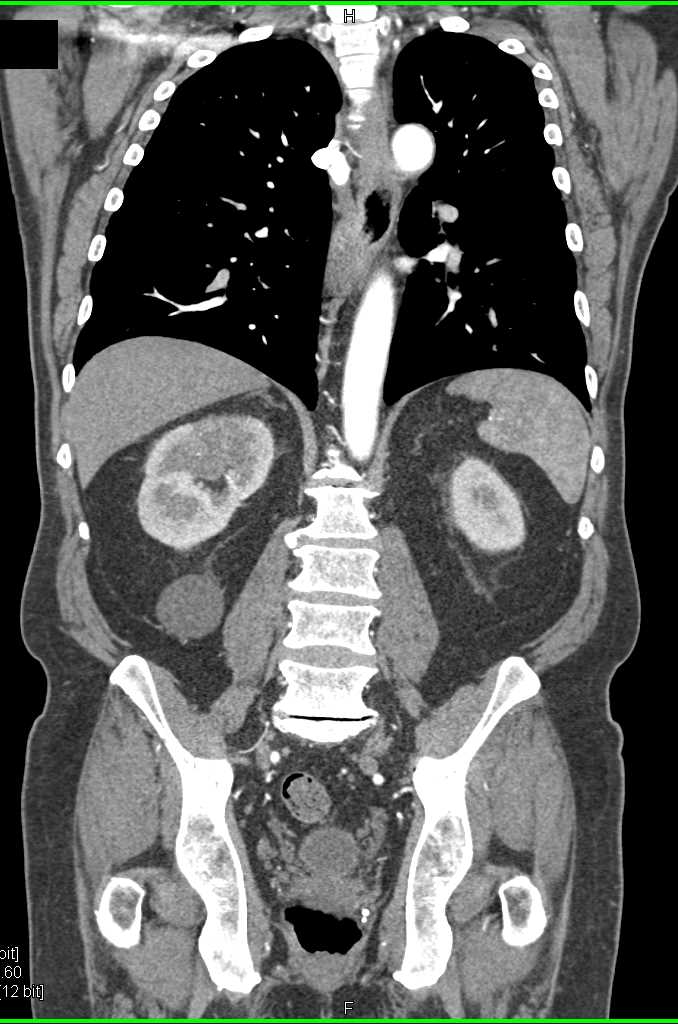

Acute Pyelonephritis Right Kidney